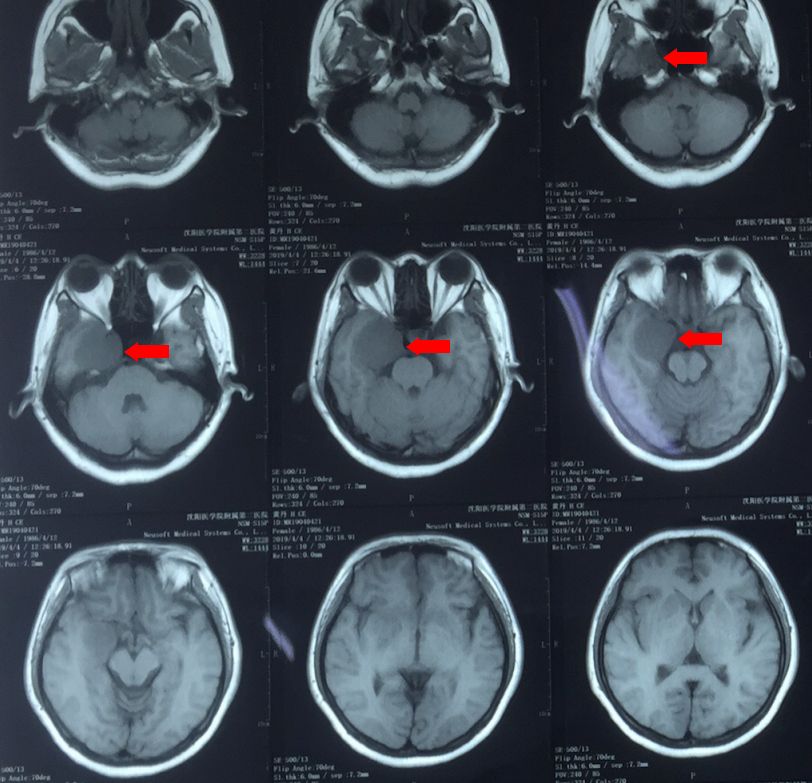

头CT:右侧海绵窦区可见类圆形高密度影,密度均匀,边缘较清晰,与正常组织界限清楚,考虑颅脑肿瘤可能性大。

颅脑核磁平扫加增强:右侧海绵窦区可见类圆形长T1长T2信号,增强可见均匀强化,大小约36x41x35mm,病灶边缘清晰,无含铁血黄素带,周边脑组织无明显水肿表现,右颈内动脉海绵窦段部分包绕。

颅脑核磁T1W1成像

颅脑核磁T2W1成像

颅脑核磁增强扫描

根据影像学特点,诊断为海绵窦内巨大海绵状血管瘤可能性大。